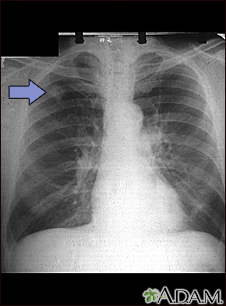

Adenocarcinoma - chest x-ray